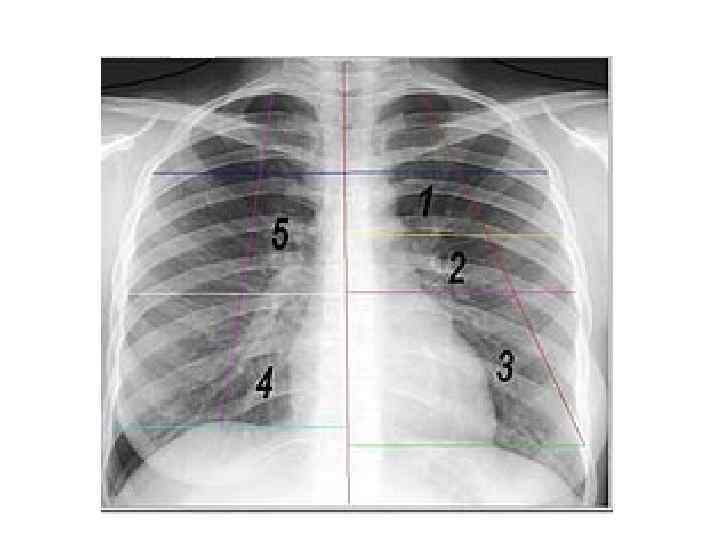

Проекция сердца и крупных сосудов на грудную клетку

Проекция полостей сердца

Перкуссия сердца Цель: определение границ относительной (реже абсолютной) тупости сердца и сосудистого пучка Границы относительной тупости сердца Левая – на 1 -2 см кнутри от левой срединноключичной линии. Образована левым желудочком. Верхняя – в 3 м/р по левой окологрудинной линии. Образована левым предсердием. Правая – на 1 -1, 5 см кнаружи от правого края грудины в 4 м/р. Образована правым предсердием.

Перкуссия сердца Границы абсолютной тупости сердца: Левая – на 2 см кнутри от границы относительной тупости Верхняя – на 1 м/р ниже границы относительной тупости Правая – по левому краю грудины Абсолютная тупость образована правым желудочком (место пункции перикарда, внутрисердечных инъекций)

Перкуссия сердца

Гипертрофия левого желудочка

Гипертрофия левого желудочка и левого предсердия

Сосудистый пучок Образован: Справа – верхняя полая вена, восходящая аорта Слева – лёгочная артерия, нисходящая аорта Определяется тишайшей перкуссией во втором межреберье. В норме не выходит за края грудины, 5 -6 см

Сосудистый пучок